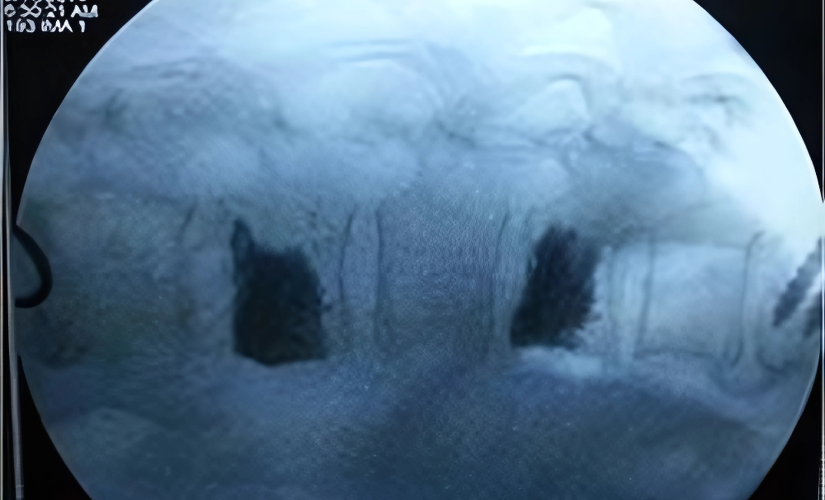

Many people with osteoporosis do not experience any symptoms until a fracture occurs. Compression fractures of the vertebrae, without associated motor or sensory weakness, can be treated with minimally invasive procedures such as vertebroplasty or kyphoplasty. These involve inserting biological cement into the vertebral body using a long needle under local anesthesia with image guidance (C-arm). Osteoporosis is diagnosed by radiography and by measuring bone mineral density (BMD). Treatment with medications is usually lifelong to maintain bone strength and prevent fractures.

Preventing osteoporosis involves a combination of adequate calcium and vitamin D intake, regular weight-bearing exercise, and avoiding smoking and excessive alcohol. Early diagnosis through bone density testing helps identify those at risk. Treatment focuses on strengthening bones, preventing falls, and managing pain or fractures when they occur. Vertebroplasty and kyphoplasty provide effective relief and stabilization for vertebral compression fractures, improving quality of life.

With minimally invasive procedures like vertebroplasty or kyphoplasty using bone cement to stabilize the spine.